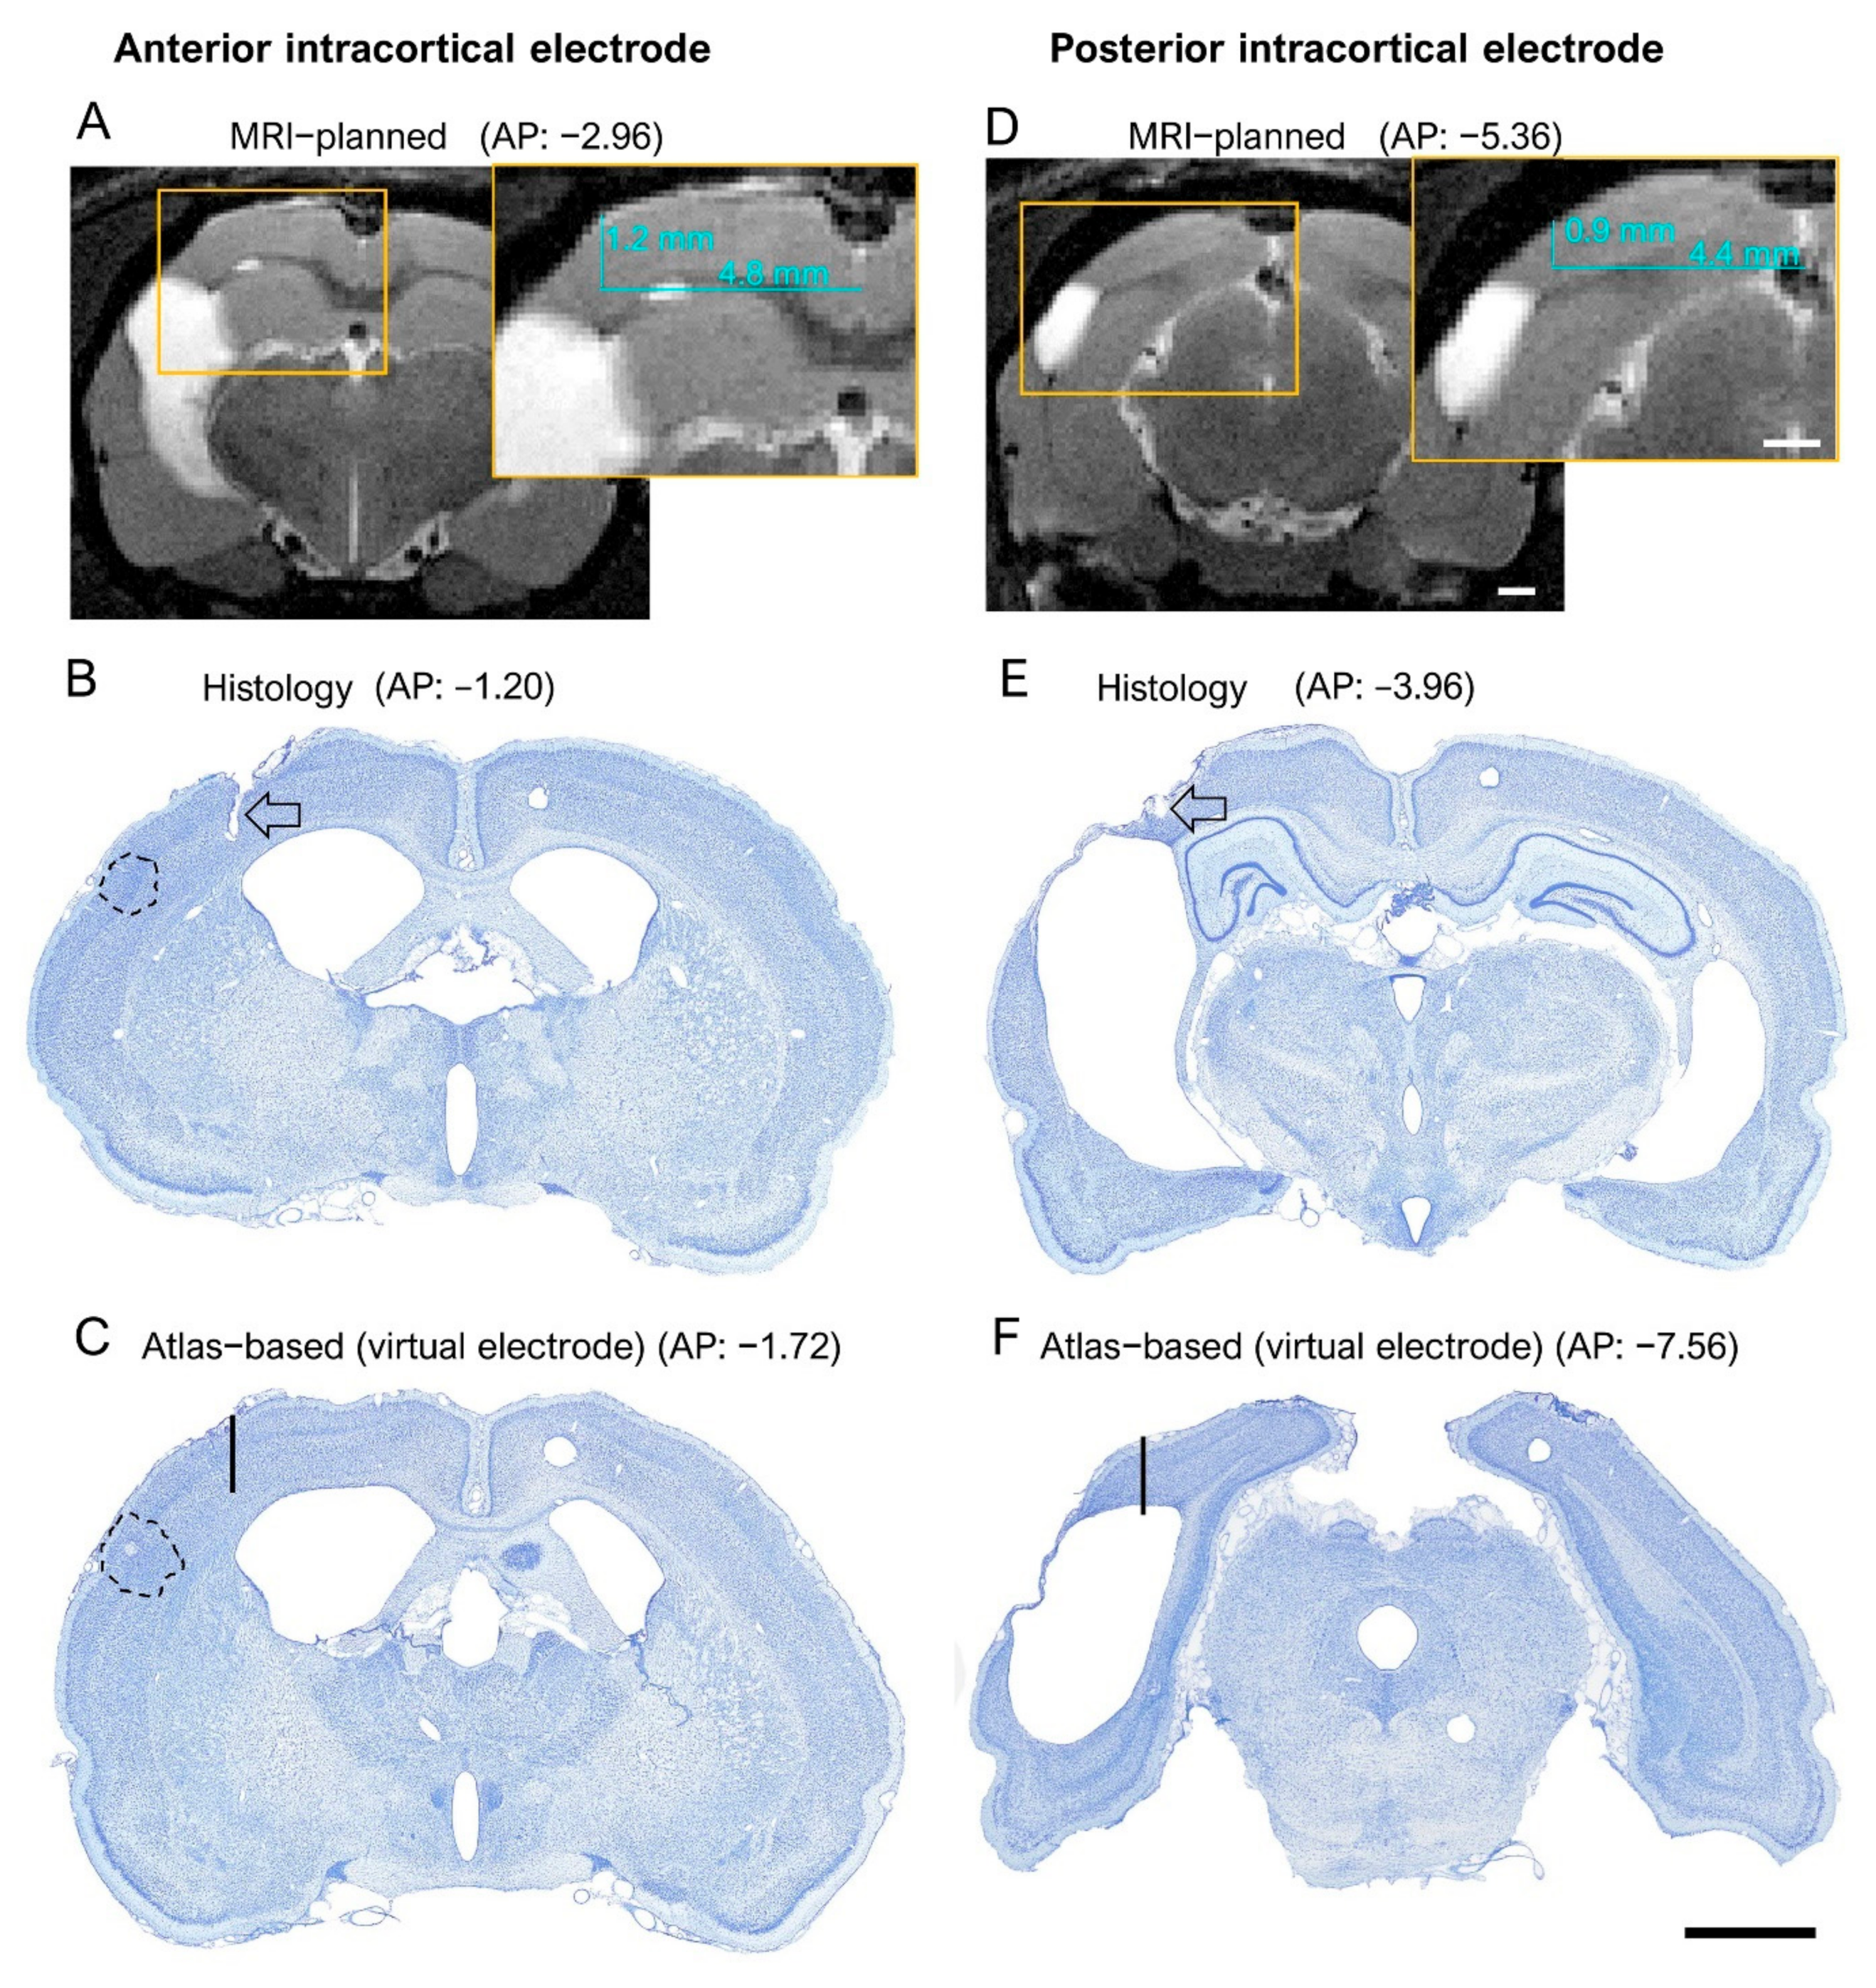

Finally, to assess whether the MRI images indeed improved the targeting of the electrode tip to the perilesional cortex, and not, for example, to the lesion cavity, we reexamined the histological sections of TBI rats in the MRI cohort. We focused on the caudal aspect of the brain, as targeting this area without the use of MRI was challenging due to remarkable TBI-related cortical atrophy.

A hypothetical “virtual” electrode was placed at the atlas-defined coordinate of the posterior intracortical electrode (Figure 10). We then reconstructed the destination of the electrode tip in the available histological sections by assessing (a) whether it was located in the cortex or lesion cavity and (b) the distance of the tip from the lesion edge. We found that by using the atlas-based coordinate (AP −7.56), 58% (18/31) of the electrodes had been in the lesion cavity compared with 0% for the MRI-guided implantations (Figure 5C and Figure 10 and Table 2). The remaining 42% (13/31) of the “virtual” electrodes were located medial to the lesion cavity, except in one case (rat 1103), in which the tip location was caudal to the lesion. The average distance of the electrode tip to the lesion edge was 0.64 ± 0.1 mm (range: 0–1.3 mm) (see also Supplementary Table S2 for further details).